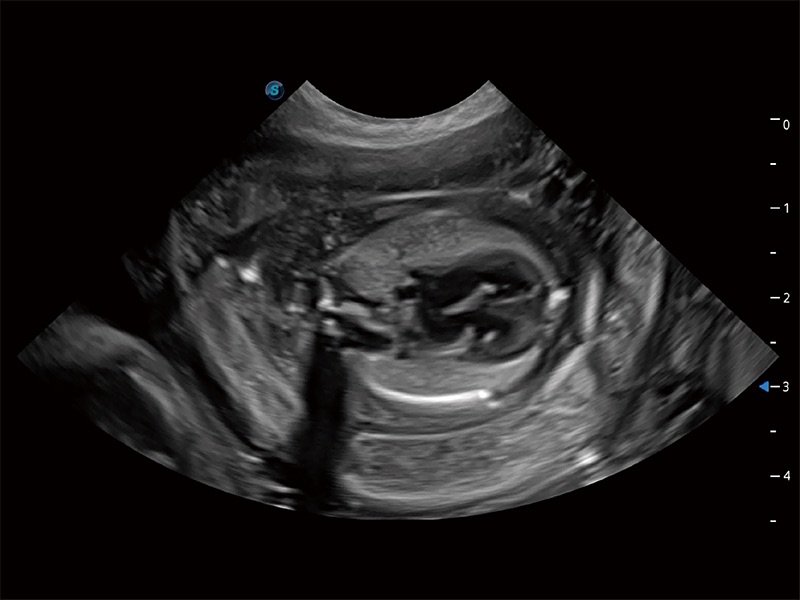

ProPet 80 专为动物医生设计,对不同的动物体型和生理结构作出了针对性的优化。通过动物影像专用软件,可满足个性化的应用需求,帮助动物医生获得更精确的诊断数据。

提供解剖示意图、标准超声图像、扫查手法涂和操作者实时检查图像,指导操作者进行标准切面的正确扫查。